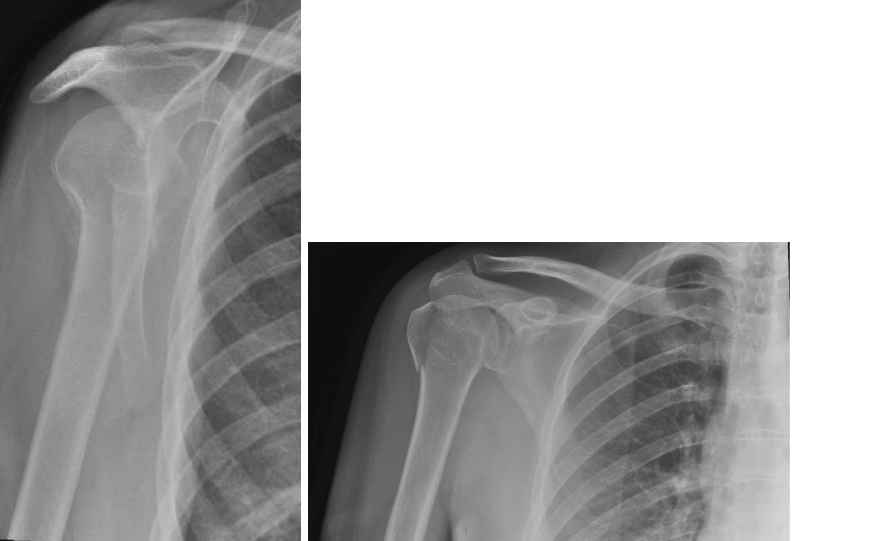

A 35-year-old woman fell from a ladder, injuring her right shoulder. These are her radiographs. 1. What do th…